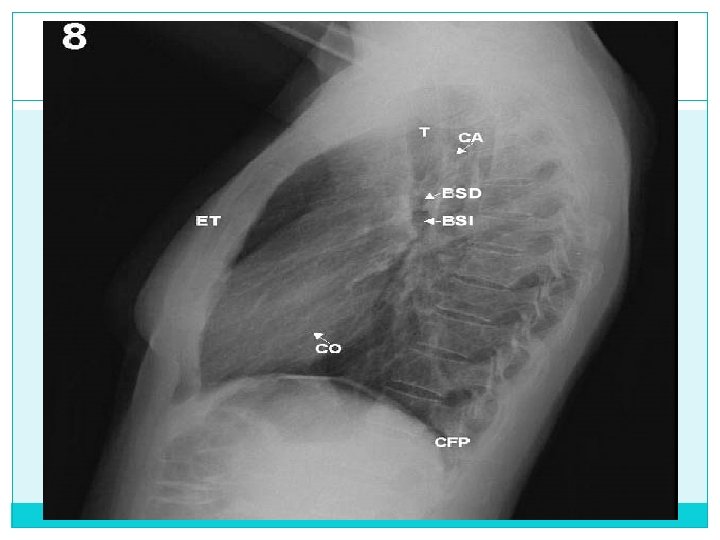

b) Torácica Forma Neonato: costillas horizontales, “pantalla de lámpara” Niño: más alargado Trastornos del crecimiento Mineralización Pared torácica Tejidos blandos (Piel, grasa subcutánea, músculo) Tejidos óseos (Costillas, clavículas, columna, esternón) Pleura

Diafragma - Diafragma derecho * Recién nacido a nivel del octavo arco costal posterior * Lactante 9 y 10 arco costal posterior - Elevación por dilatación - Elevación de un hemidiafragma … parálisis del nervio frénico - Parálisis…. . Absceso

Pleura - Angulos costofrénicos nitidos - Cisura mayor va de T 4 hacia abajo y adelante - Cisura menor casi horizontal desde el hilio derecho - Derrame pleural * Menisco basal …. . De pie * Menisco apical…. . . Decúbito dorsal * Sin cambio …. . Loculado - Neumotorax * Acumulación de aire * Aumento del espacio pleural

CISURAS.